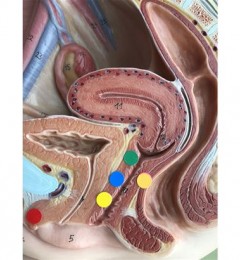

图一:返流性食管炎动态DR造影图像

图二:食道良性狭窄(腐蚀性)